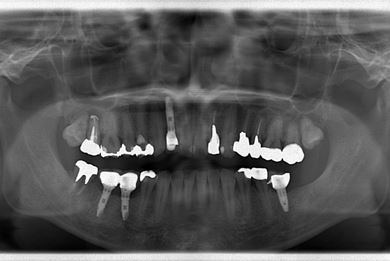

| 性別/年齢 | 男性 / 36歳 | ||||||||||||||||||||||||||||||||

| 治療方針 | 抜歯と同時にインプラント埋入を行い、治療期間を短縮する。 | ||||||||||||||||||||||||||||||||

| 治療内容 | インプラント4本(抜歯即日スピードインプラント)、メタルボンドセラミッククラウン4本 | ||||||||||||||||||||||||||||||||

| 総治療費 | 1,457,888円 | ||||||||||||||||||||||||||||||||

| 治療期間 | 1年7ヶ月 |